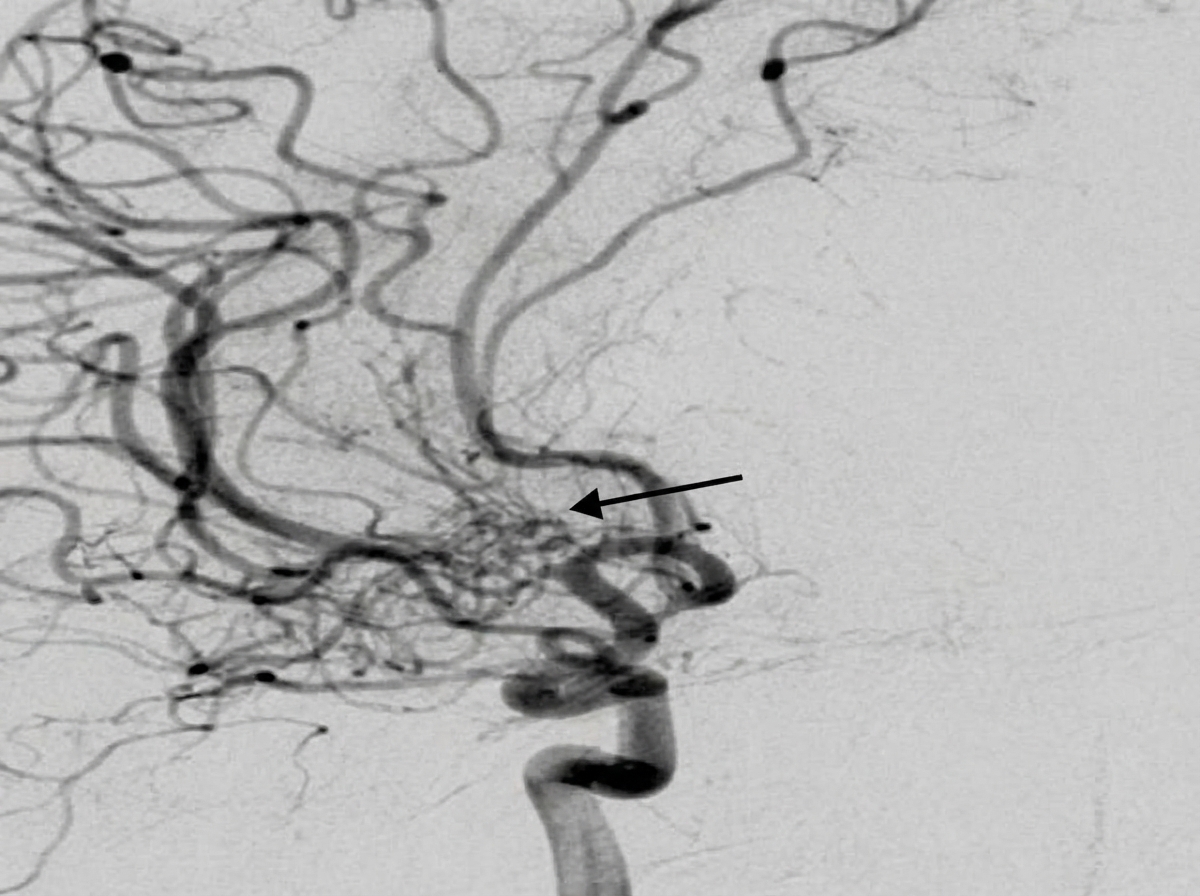

A 20-year-old man from hilly areas presented with epistaxis. DSA showing the sphenopalatine branch of the maxillary artery is provided. The arrow most likely points to which pathology?

Explanation: ***Arteriovenous Malformation (AVM)*** - **DSA** shows characteristic **nidus** with early venous filling and abnormal vascular tangle in the **sphenopalatine territory**, typical of cerebral AVM. - Young males from **hilly areas** (high altitude) have increased risk of **cerebral AVMs** due to chronic hypoxia and vascular stress. *Rhinosporidiosis* - A **fungal infection** causing **nasal polyps** with characteristic **sporangia**, not vascular abnormalities on DSA. - Would show **soft tissue masses** on imaging, not the vascular nidus pattern seen in AVMs. *Angiofibroma* - **Juvenile nasopharyngeal angiofibroma** appears as a **hypervascular mass** with intense contrast enhancement but lacks the **nidus pattern**. - Typically arises from the **sphenopalatine foramen** as a solid tumor, not tangled vessels with early venous drainage. *Pseudoaneurysm* - Shows a **saccular outpouching** with contrast pooling and delayed washout, not the tangled vessel pattern. - Usually results from **trauma** or **infection**, presenting as a focal arterial wall defect rather than a nidus.